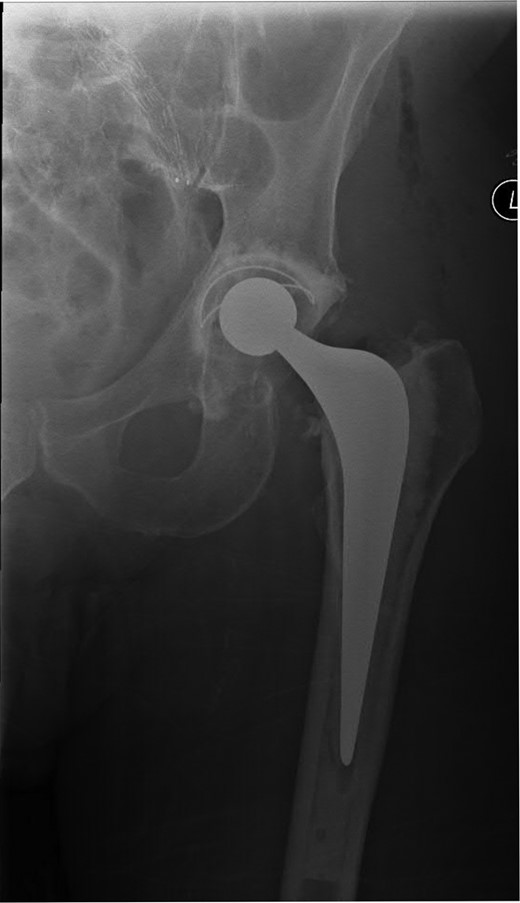

A 74-year-old male was admitted with an intracapsular fractured left neck of femur (Fig. 1). According to the NICE guidelines, he received a cemented THR (Fig. 2) via the posterior approach in the lateral decubitus position. Five weeks prior, he had an EVAR for a leaking AAA. Due to a calcified, narrow right common iliac artery (CIA), the EVAR consisted of a left aortouniiliac endograft with coil embolization of the right CIA and a femoro-femoral crossover graft (Figs 3 and 4).

Lateral radiograph of the lumbar spine demonstrating the aortouniiliac EVAR with coil embolization of the right CIA.